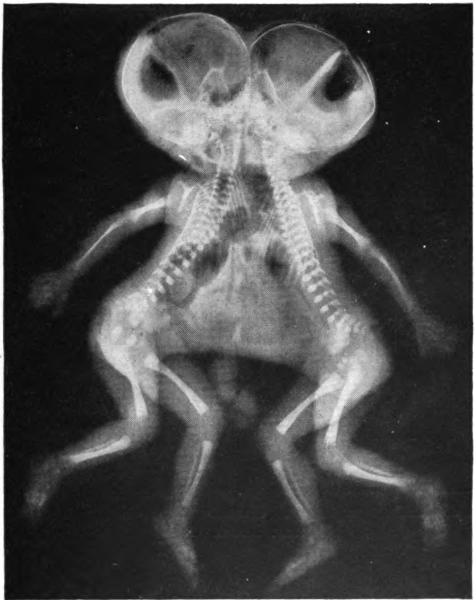

They were united from the bottom tip of the sternum (or xyphoid) down to the pelvis in a position that compelled them to face one another. Unable to stand, they were in a lying down position at baseline.

Each had a dominant kidney that used the same bladder as a reservoir. Additionally, they shared one liver. They had four arms and three legs. There was one anus along with a nearby tiny opening that reflected a duplication. And so on.

The photo accompanying this piece at the top of the article is not from the case discussed. As you can tell in the x-ray picture of conjoined twins there are fundamental differences, for one, there are four legs.